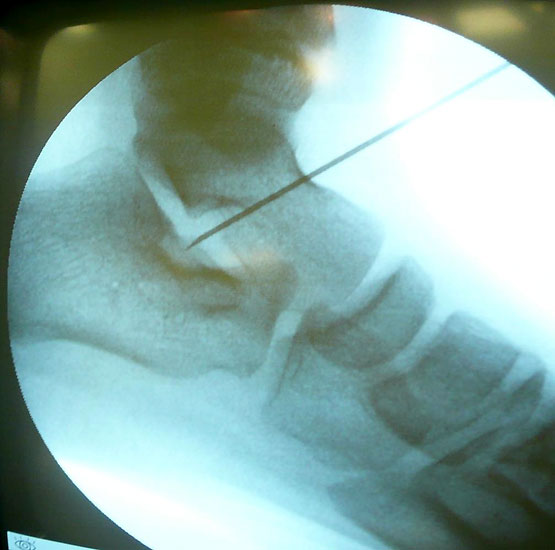

Abwaschen und steriles Abdecken beider Füße in Rückenlage und Unterschenkelblutleere (Abb. 1). Ertasten des Sinus Tarsi, zur genaueren Lokalisation Verwendung einer Kanüle (Abb. 2) um die korrekte Position über dem Eingang zum Sinus tarsi unter Bildverstärker zu kontrollieren. Über einen 1-2cm messenden Hautschnitt (Abb. 3) erfolgt nun die Präparation des Eingangs zum Sinus tarsi durch stumpfe Präparation. Die Knochenoberfläche des Calcaneus am tiefsten Punkt des Sinus tarsi wird dargestellt, unterstützt durch eine manuelle Rückfußinversion. Nach Markieren der korrekten Eintrittstelle mit einem Kirschnerdraht und anschließender Bildwandlerkontrolle (Abb. 4) wird nun die calcaneare Eintrittstelle in ca 20° Kippung nach lateral und dorsal mit einem 3,2mm Bohrer aufgebohrt.

Hierbei ist darauf zu achten, einerseits den Eintrittspunkt nicht zu weit lateral zu wählen um eine Aussprengung der lateralen Calcaneus-Corticalis oder Kompromittierung der Peronealsehnen beim Bohren oder Eindrehen der Spongiosaschraube zu vermeiden, andererseits das Calcaneo-cuboidale Gelenk (C-C-Gelenk) nicht zu verletzen. Nach Gewindeschneiden und Längenmessen Einbringen einer 6,5 mm Titan-Spongiosaschraube mit durchgehendem Gewinde und einer Länge von durchschnittlich 25 bis 35mm. Der Abstand zum C-C Gelenk sollte mindestens 10 mm betragen.